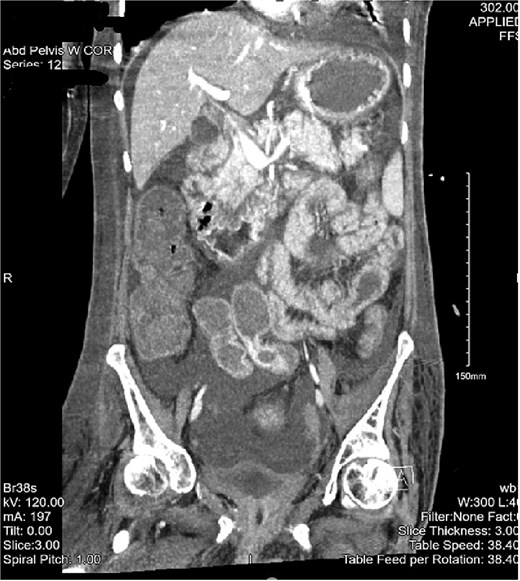

The patient then began having continuous bloody bowel movements with requirements for multiple blood transfusions. CT angiogram of the abdomen and pelvis demonstrated wall thickening of the cecum/ascending colon and distal active extravasation of contrast (Figs 3 and 4). These findings were consistent with a cecal mass. A massive transfusion protocol was initiated and interventional radiology was emergently consulted for angioembolization.

CT angiogram of the abdomen and pelvis—arterial phase with a coronal cross section. Patchy contrast extravasation is observed in the ileocecal region with adjacent distal wall-thickening. Distended loops of small bowel with mesenteric fat stranding are observed. Significant abdominopelvic free fluid is seen, correlating with ascites. Enlarged mesenteric lymph nodes are observed.

CT of the abdomen and pelvis with a coronal cross-section. Asymmetric wall thickening is observed in the cecum and ascending colon with adjacent fat stranding. Proximal dilation of small bowel loops with mesenteric stranding is also seen. Significant abdominopelvic free fluid is demonstrated. The CT findings correlate with mass versus inflammatory colitis. The read was addended to reflect concerns for cecal mass.